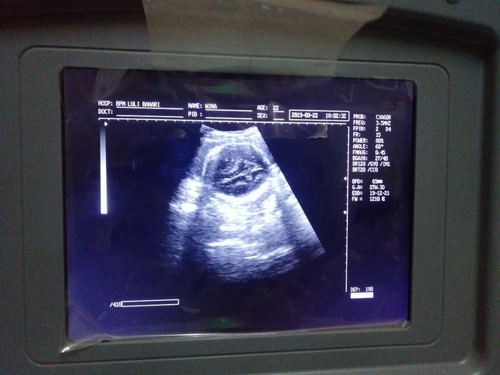

USG

Bun aq dah usg tp ko gambarnya bgtu y...

UK 27w 3d ya bun? Klo udh gede hamilnya, usg nya per bagian anggota tubuh. Ga keliatan janin secara utuh 1 gambar. Itu kan kaya bulet2 gitu, klo ga kepala, lingkar perutnya bun. Kemungkinan besar itu kepala bun, yg ditengahnya itu bersekat2 otaknya. Saya jg klo usg krn udh gede dokternya ngasih tau satu2. Ini kepalanya, pahanya, punggung sm pantat, perut, jantung gitu2. Next usg bundanya harus aktif lg ya komunikasi sm dokternya, sayang usg kan mahal bun ๐

Itu gambar diambil pas di monitor usg ya bun? Bukan print hasil usg. Spertinya itu masih proses dokter mencari posisi janin yg pas. Jadi itu bukan hasil akhir usg. Mungkin saat usg bunda harus lebih aktif lg tanya sm dokter. Biar tdk bingung ya bundaโบ๏ธ

Kok gambarny gt y bun, jd bgung. Apa alat usgny kurang bagus y? Aku 27w di alat usgny dh nampak jelas mana kepala tangan dll, cb cr dokter yg alat usg ny bagus bun sm sm usg dan bayar cb bund cr yg bagus